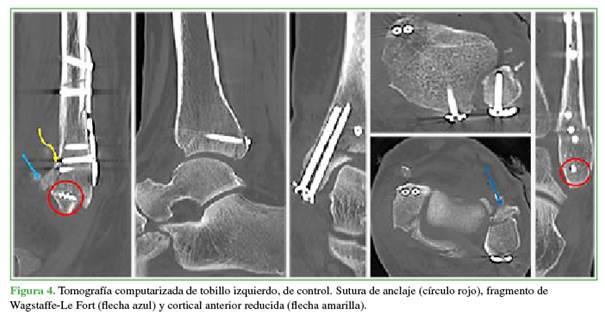

La paciente quedó hospitalizada para el manejo del dolor y para una tomografía computarizada en la que se observó la reducción adecuada de las fracturas, sin pérdida de la congruencia tibio-astragalina (Figura 4). La evolución fue adecuada tras cuatro semanas sin apoyo, terapia física y luego apoyo progresivo de la extremidad. A los seis meses, tenía una marcha sin dolor y un puntaje de la AOFAS de 82. Las fracturas habían consolidado (Figura 5).